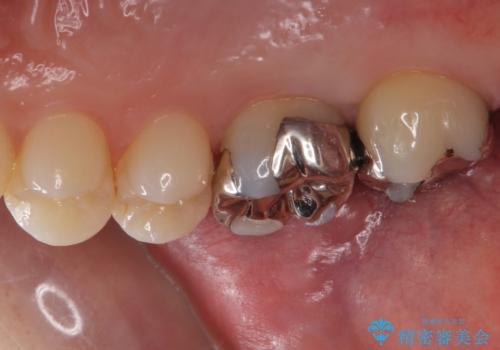

- 銀歯を白くしたいとのことで来院されました。

詰め物が覆っている面積が大きいため、強度を考慮してセラミックインレーではなくクラウンでの修復処置を進めていきます。

奥歯で咬合力の負担を考慮した結果、インレーやアンレーではなくクラウンをおすすめする場合があります。